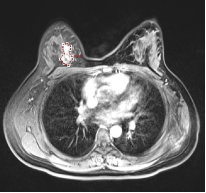

2.1 直方图特征(Histogram Features) 本类特征主要通过统计病灶部位的灰度强度信息(或亮度信息),然后考察病灶部位灰度强度信息的整体分布情况。图2分别描述的是带病灶的乳腺MR图像,其中病灶部位用红色的多边形线段标识出来。假设对图2.a和2.b的病灶部位求直方图特征,将有如下情况:

a b 图2. 带病灶的乳腺MR图像; 红色多边形表示病灶区域

Mean:均值,描述的是图像整亮度信息,若亮度越大,则Mean越大。假设图2.a病灶部位的亮度信息小于图2.b,则可以表达为Mean& #40;2.a& #41;< Mean& #40;2.b& #41;; Variance:方差,描述的是图像亮度信息的变化,若变化程度越大,则Variance越大。假设图2.a病灶部位的亮度变化小于图2.b,则可以表达为Variance& #40;2.a& #41;< Variance& #40;2.b& #41;; Unifomity:均匀性,描述图像亮度信息的均匀程度,若均匀程度越大,则Unifomity越大。假设图2.a病灶部位的均匀程度大于图2.b,则可以表达为Unifomity& #40;2.a& #41;> Unifomity & #40;2.b& #41;; Skewness:偏度,描述图像亮度信息分布的偏向性,若图像明亮区域信息比灰暗区域信息分布多,则Skewness值为正。如图2可知,Skewness& #40;2.a& #41;为负,Skewness& #40;2.b& #41;为正; Kurtosis:峰度,描述图像亮度信息的集中程度,若集中程度越大,则Kurtosis值越大;假设图2.a病灶部位亮度信息集中程度小于图2.b,则可以表达为Kurtosis& #40;2.a& #41;<Kurtosis & #40;2.b& #41;; Energy: 能量,描述图像亮度信息变化的剧烈程度,若变化越小,则Energy越大;如图2可知,Energy& #40;2.a& #41;>Energy& #40;2.b& #41;; Entropy:熵,描述图像亮度信息分布的复杂程度,若分布越复杂,则Entropy越大;假设图2.a病灶部位亮度信息复杂程度小于图2.b,则可以表达为Entropy & #40;2.a& #41;<Entropy & #40;2.b& #41;。